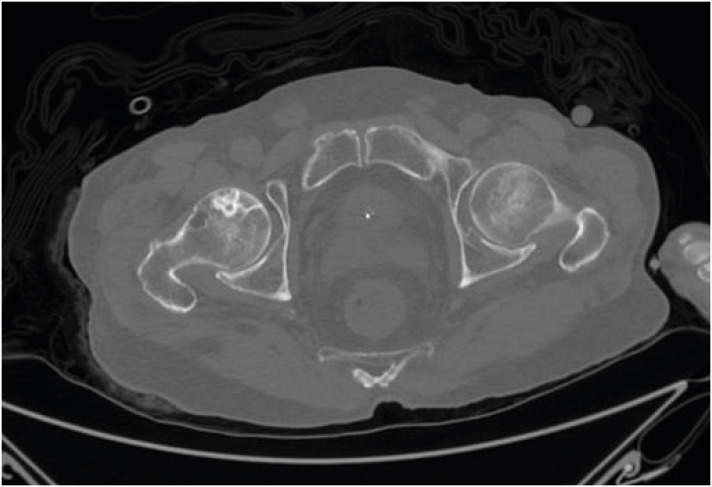

Fig. 1). Low-density regions and fractures of the right femoral head in abdominal computed tomography (CT) images, which bone necrosis was assumed to have redounded (

Fig. 2). A chest X-ray was taken at the time of the ED visit, and no pathological findings were observed (

Fig. 2 Osteonecrosis of the right femoral head. Abdominal computed tomography axial view (window width: 2501, window level: 250).